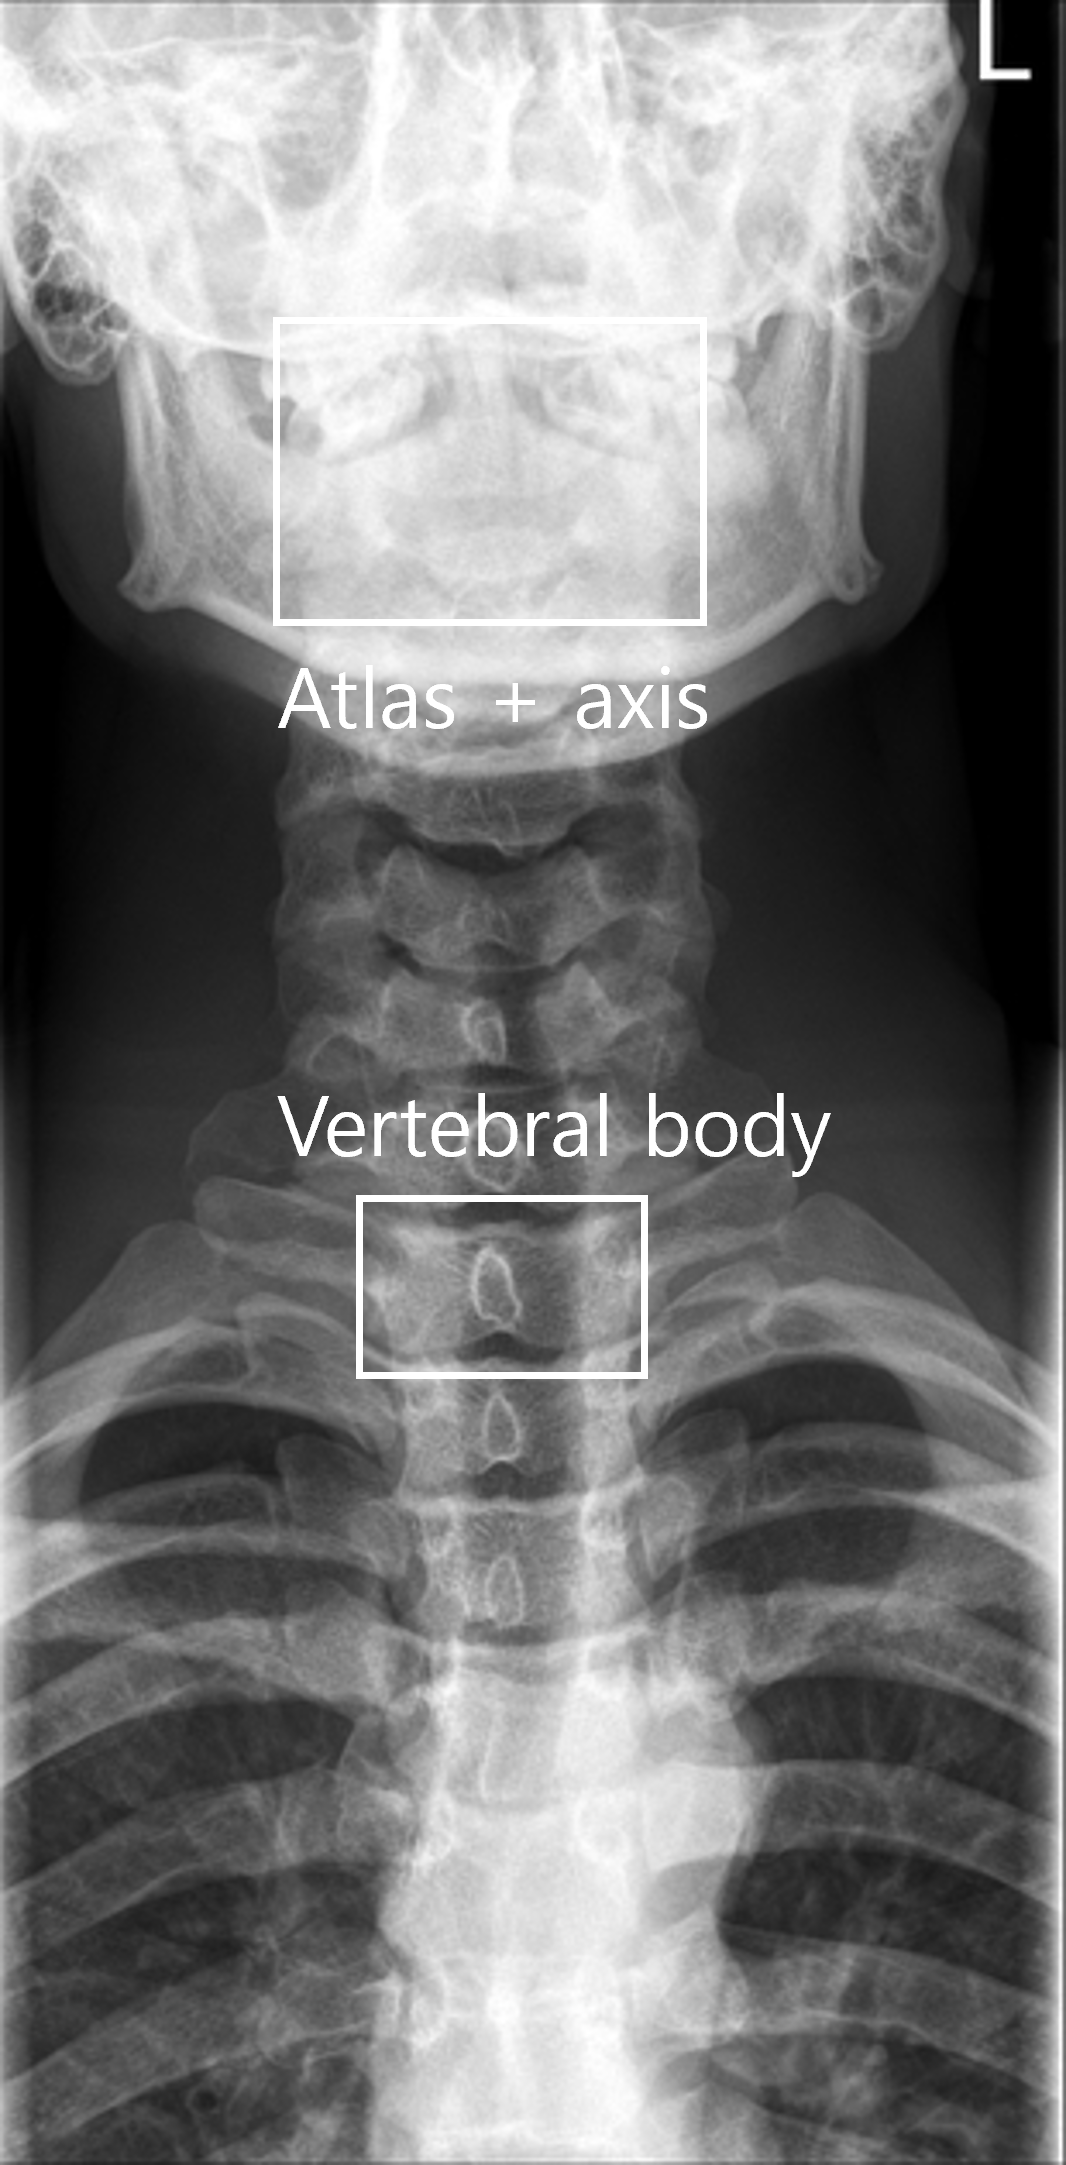

AI 모델이 의료 영상을 효과적으로 학습할 수 있도록, 각 부위와 촬영 방식(AP, Lateral 등)에 맞추어 세그멘테이션(Segmentation), 키포인트(Keypoint), 바운딩 박스(Bounding box) 등 세 가지 방식의 정밀 라벨링 작업을 복합적으로 수행했습니다.